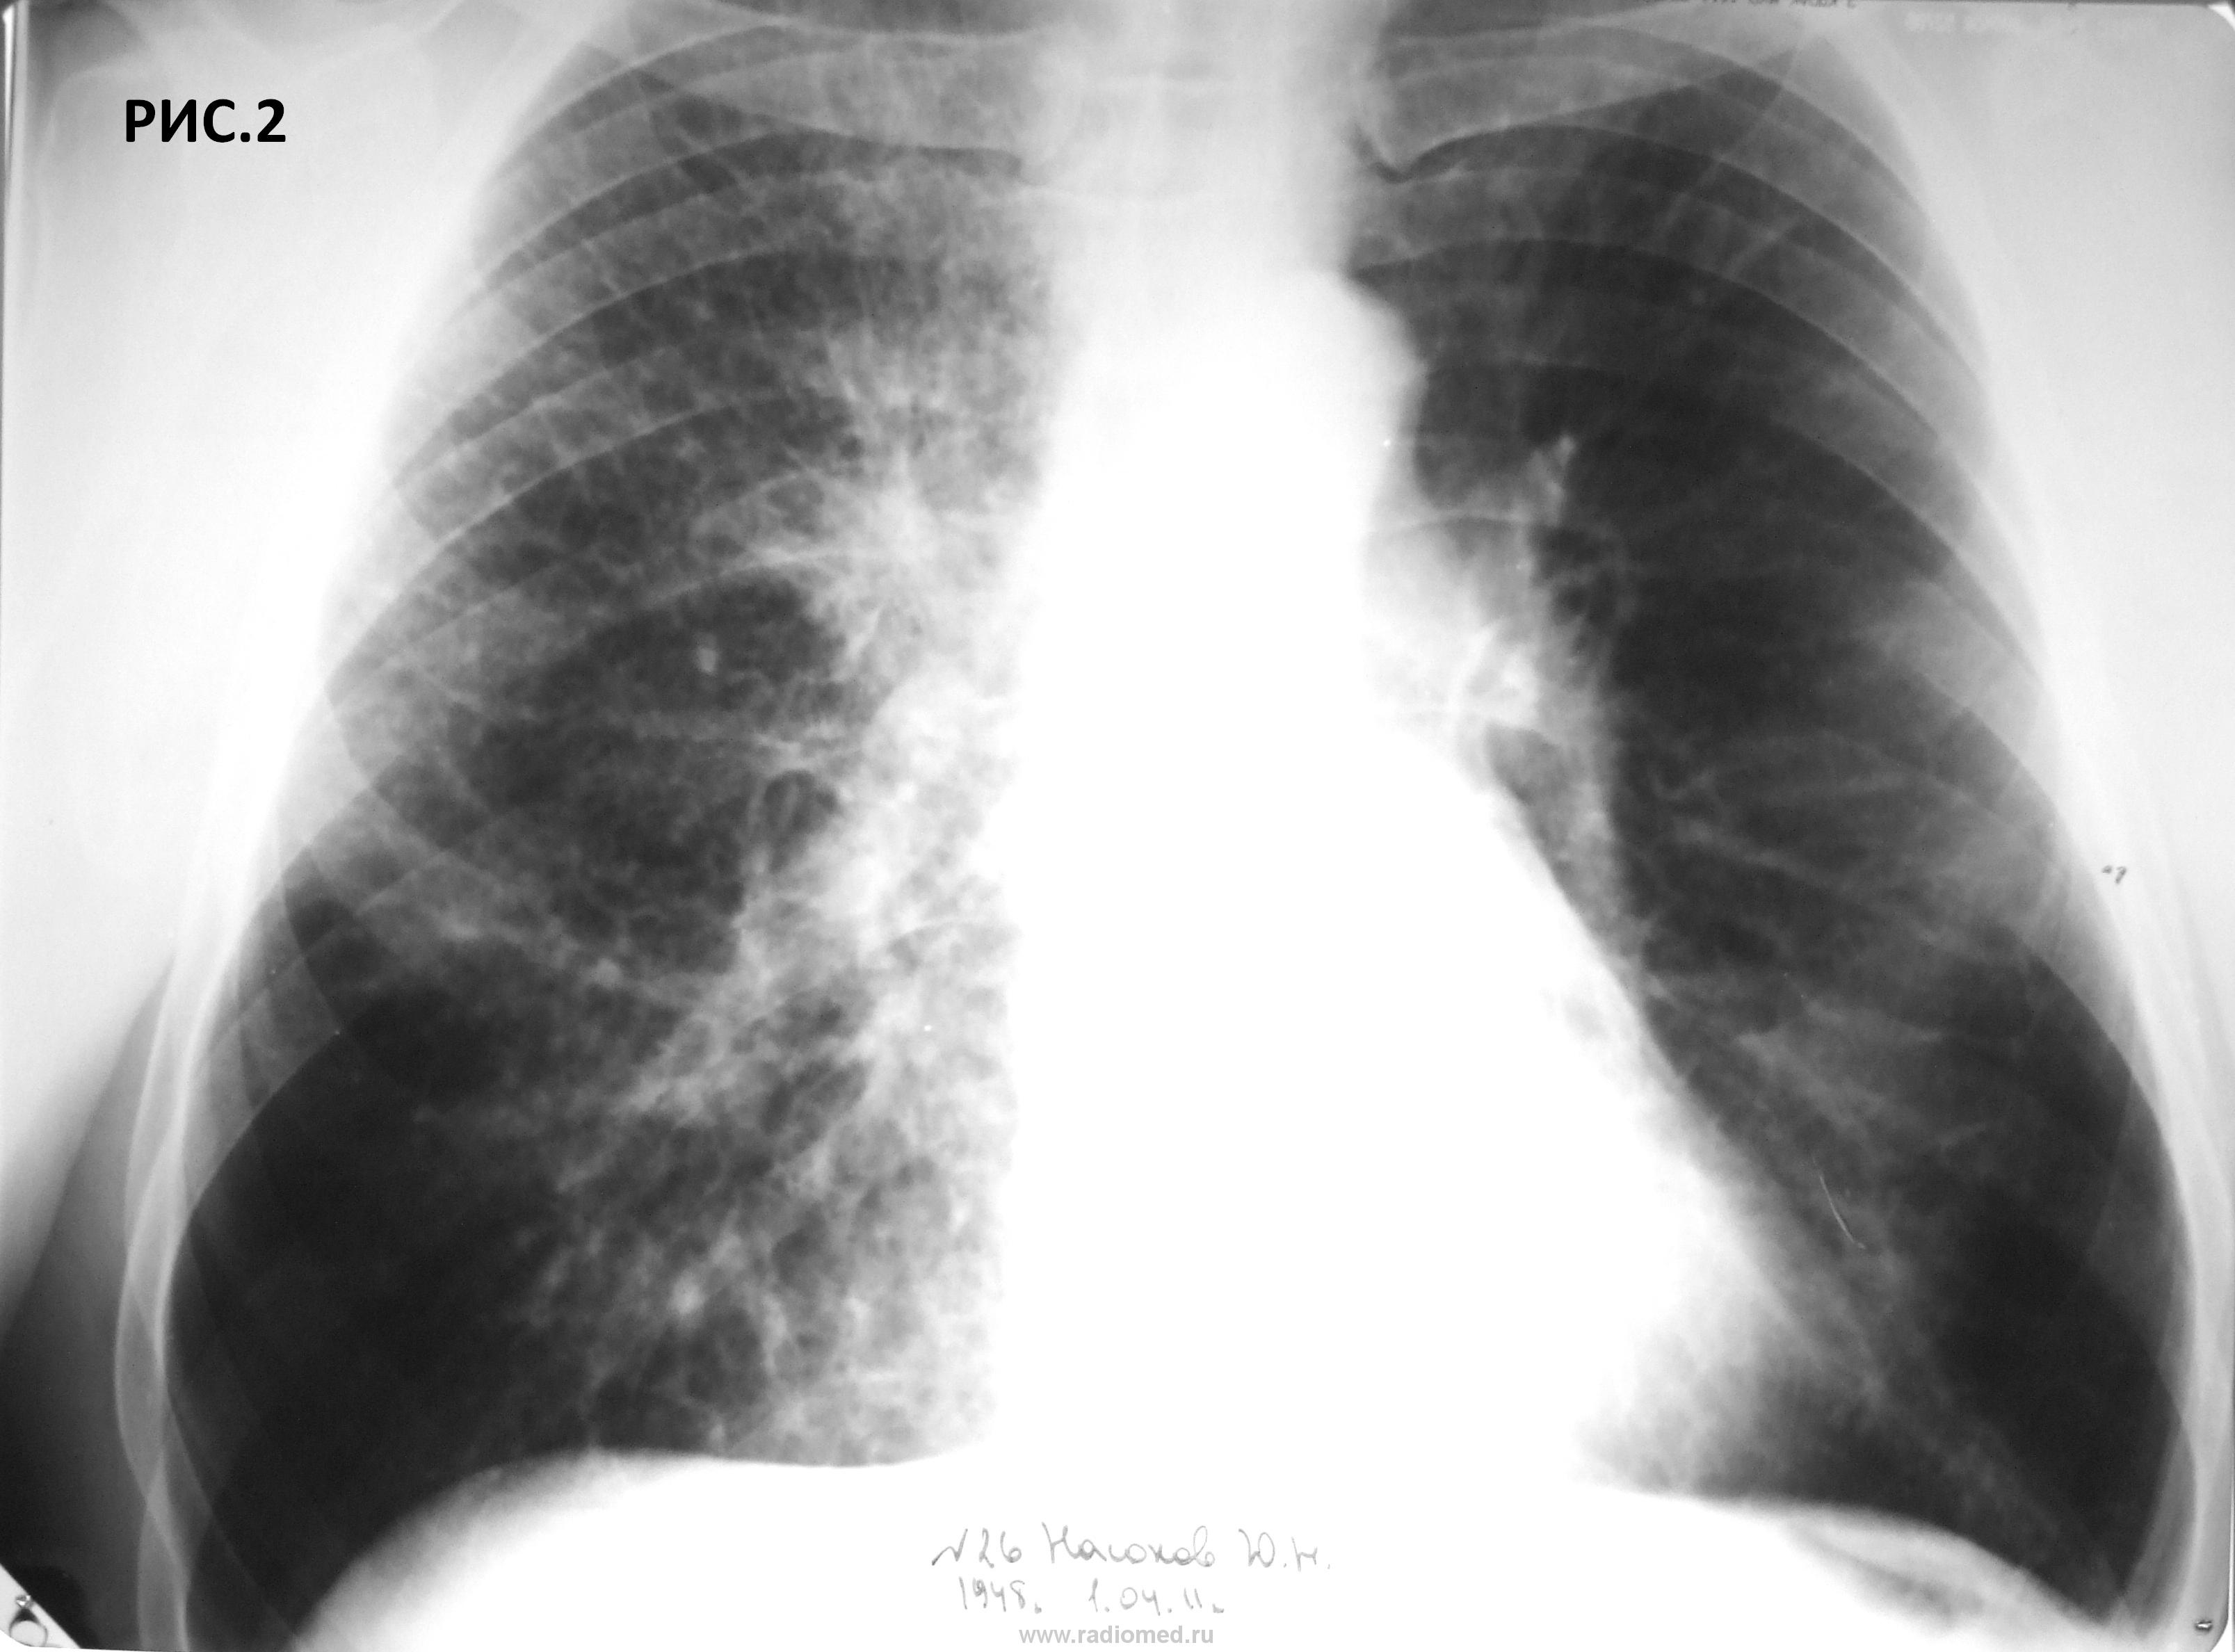

Больной 63, крановщик, курильщик. Перенес левостороннюю пневмонию 15.12.2010 (рис.1). В течение 10 дней до рентгенографии грудной клетки от 1.4.2011 (рис.2.3.4) беспокоит сухой кашель. Температура тела нормальная. С уважением Nikolas

Прозрачность левого легкого представляется повышенной за счет?

Левый корень уплотнен и расположен ниже обычного.

Средостение умеренно смещено влево.

Левый купол диафрагмы выше обычного.

Всё страшнее правый корень, всё неструктурнее и мохнатее. Как бы не было тут худо... Такие коренья - показание для направления на КТ и бронхоскопии, но это моё мнение.

Угу, "голый" корень, средостение то сместилось влево.

Согласен с doktor-rentgen. По этой же причине повышена прозрачность лев. лёгкого. Изображения в целом вызывают уныние, особенно первое: слишком много информации потеряно. Но нельзя отрицать уменьшения объёма в/доли пр. лёгкого. Без томографии не обойтись.

думается то что называют повышенной прозрачностью - нормальная ткань, а вот верхняя гиповентилируется, жаль на боковом не все четко как хотелось бы...или какаято неоднородная инфильтрация  есть и вдоль междолевых...а может это уже фантазии..

Смею высказаться за диффузный пневмофиброз, корни  фиброзно изменены. правый корень кажется "пушистым" за счет вышесказанной ассиметрии укладки. Теней подозрительных на увеличенные лимфоузлы в проекции корней не отмечается. Ну про разность пневмотизации легочных полей так же выше сказано. Вообщем пока ХОБЛ .